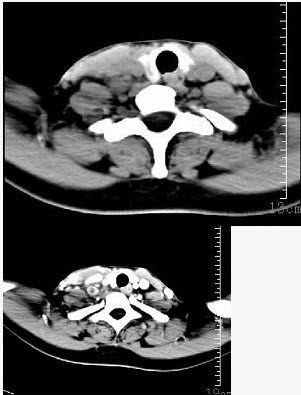

- 单项选择题女性35岁,发热、盗汗近3个月,颈部摸到多个结节,CT扫描如图所示,请选择最可能的诊断()。

- D